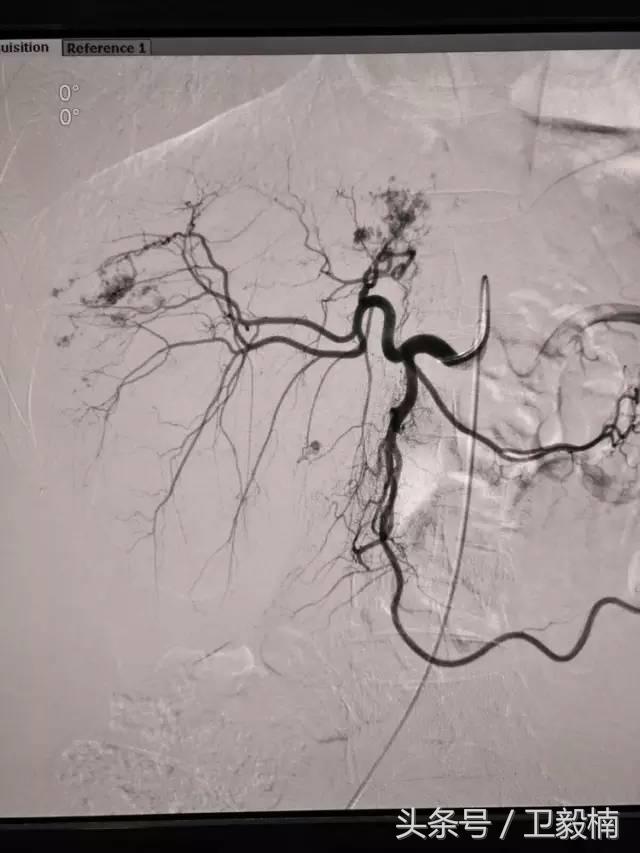

2、经导管血管栓塞法(Transcatheter embolization)

经原血管造影的导管或特制的导管,将栓塞物送至靶血管内,一是治疗内出血如外伤性脏器出血、溃疡病、肿瘤或原因未明的脏器出血。另一是用栓塞法治疗肿瘤,因肿瘤循环部分或全部被栓塞物阻断,以达控制肿瘤之生长,或作为手术切除的一种治疗手段;亦可用于非手术脏器切除,例如注射栓塞物质于脾动脉分支内,即部分性脾栓塞,以治疗脾功亢进,同时不影响脾脏的免疫功能。

(3)应用栓塞材料,钢圈,内支架治疗动脉瘤、AVM、动静脉瘘,血管性出血。

(1)选择性肿瘤供血动脉灌注化疗+栓塞治疗恶性肿瘤。

(3)应用栓塞术治疗海绵状血管瘤,蔓状血管瘤,子宫肌瘤,骨肉瘤,鼻咽部纤维血管瘤等。